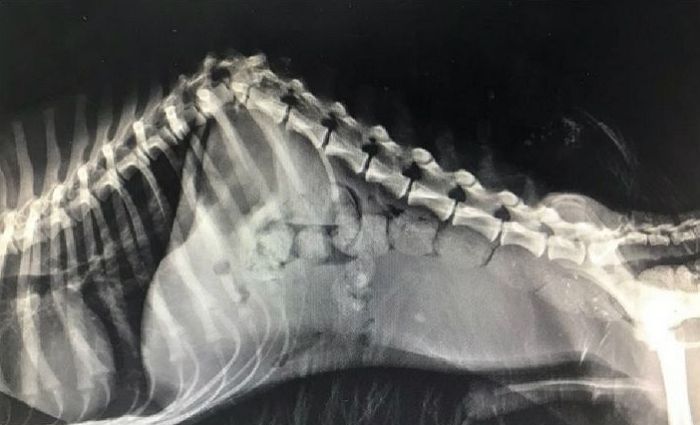

수의사는 "엑스레이 촬영 결과 교통사고 등 다른 가능성을 생각하기에는 척추 외에 다친 흔적이 보이지 않는다"라고 진단했다.

이어 "수술을 하면 생명에는 지장이 없겠으나 네 발로 다시 걷기는 사실상 불가능하다"고 덧붙였다.